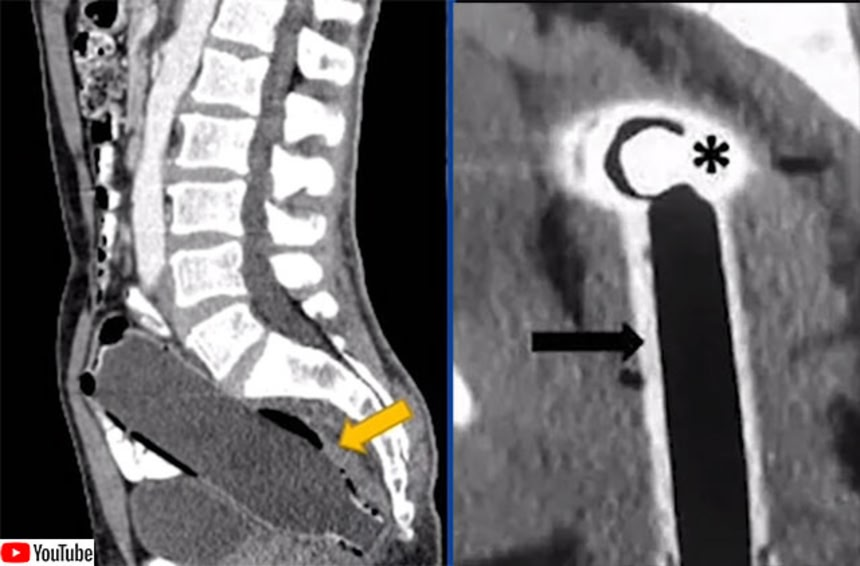

X線で捉えられた男性の直腸には、長さ20cm、幅5cmもの大きな砲弾が入り込んでいた。